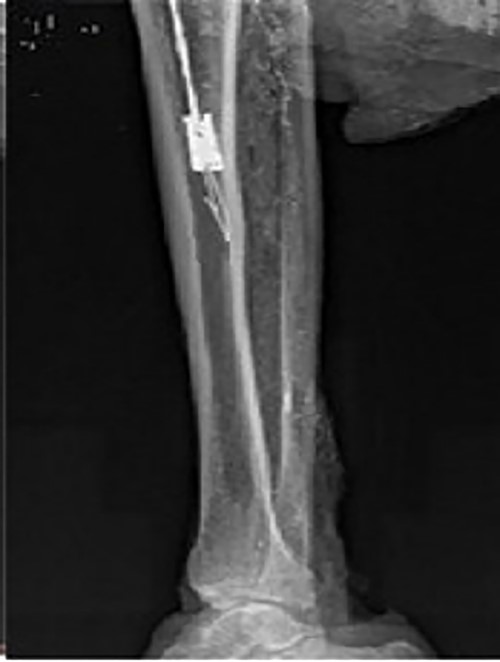

Preoperative X-ray films showing union of the right tibial fracture associated with a broken intramedullary nail remaining distal to the tibia.

A 48-year-old male patient was admitted for requesting removal of all internal implants in his body. He had a closed tibial shaft fracture caused by a collision 15 years prior and was treated with close reduction and intramedullary nailing fixation. Delayed healing occurred after the operation. A nail was broken at a distal locking screw hole. The fracture healed after plaster fixation for 3 months. The internal implant was removed 3 years after the fracture, but the distal end of the broken intramedullary nail could not be removed by the hook removal method and remained in the medullary cavity (Fig. 1). Both operations were performed in another hospital. One year prior to admission, the patient underwent open reduction and internal fixation in our hospital due to a fracture of the right distal radius, and the fracture healed after the operation. His function in the lower and upper limbs recovered well. It can be seen from the preoperative X-ray film that the remaining intramedullary nail was hollow; through measurement, it was known that the outer diameter of the broken nail was 10 mm, which was larger than the isthmus of the medullary cavity.